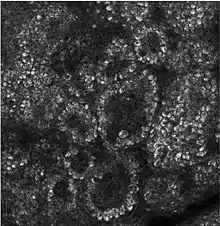

Confocal image of the stratum corneum

Composed of 10 to 30 layers of polyhedral, anucleated corneocytes (final step of keratinocyte differentiation), with the palms and soles having the most layers. Corneocytes contain a protein envelope (cornified envelope proteins) underneath the plasma membrane, are filled with water-retaining keratin proteins, attached together through corneodesmosomes and surrounded in the extracellular space by stacked layers of lipids.[11] Most of the barrier functions of the epidermis localize to this layer.[12]